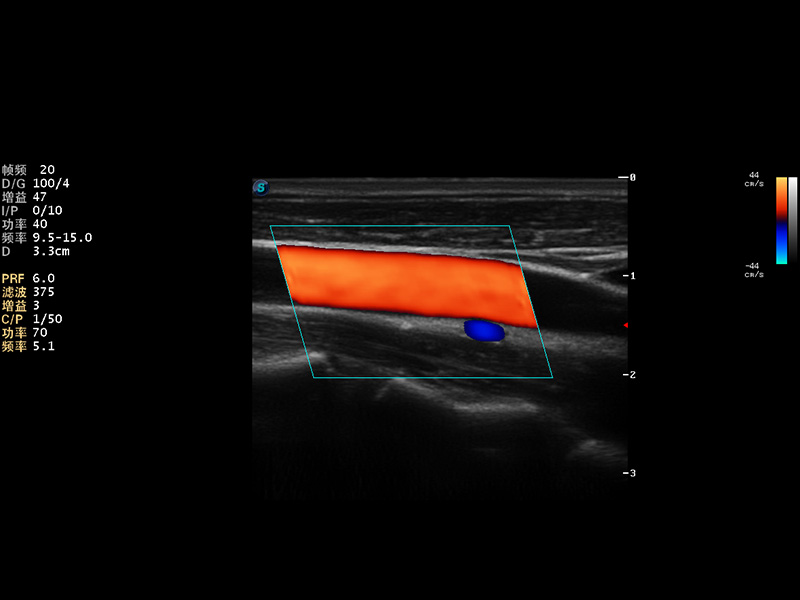

S9便携式彩色多普勒超声诊断仪是米兰官方网站研发的高端便携彩超设备,外观设计新颖、产品性能卓越。S9在便携超声领域采用了突破传统的触摸屏交互设计,并以先进的软件硬件技术和设计理念,为您带来清晰的图像质量、稳定的工作性能和便捷的操作体验。

AutoC智能血流追踪